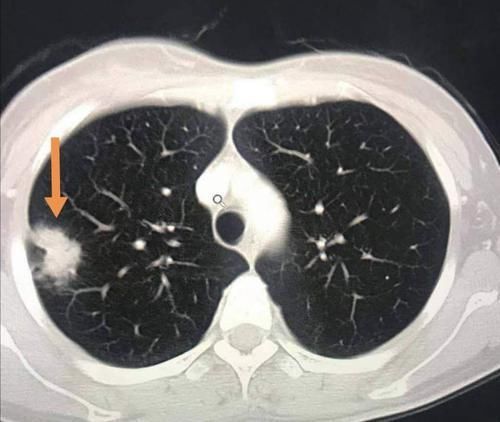

我们观察她的CT片,在她的右肺下叶有一个肺大泡(黄色箭头),紧挨着胸膜,由于气流冲击被顶破了,肺里的气体进入胸腔发生气胸。

这种少量气胸并不严重,保守观察就好,会慢慢吸收。

但我们同时又有一个意外的发现:橙色箭头是一个肺结节,

文章插图

结节外侧有胸膜牵拉,内部可以看到支气管充气征,综合分析符合一个高分化腺癌的CT表现。

这个小肿瘤没有症状,可以通过胸腔镜微创切除,手术后5年生存率接近100%。

但如果没有这个气胸发作,拖个一年半载的,等出现肺部症状再来,就不好说了。